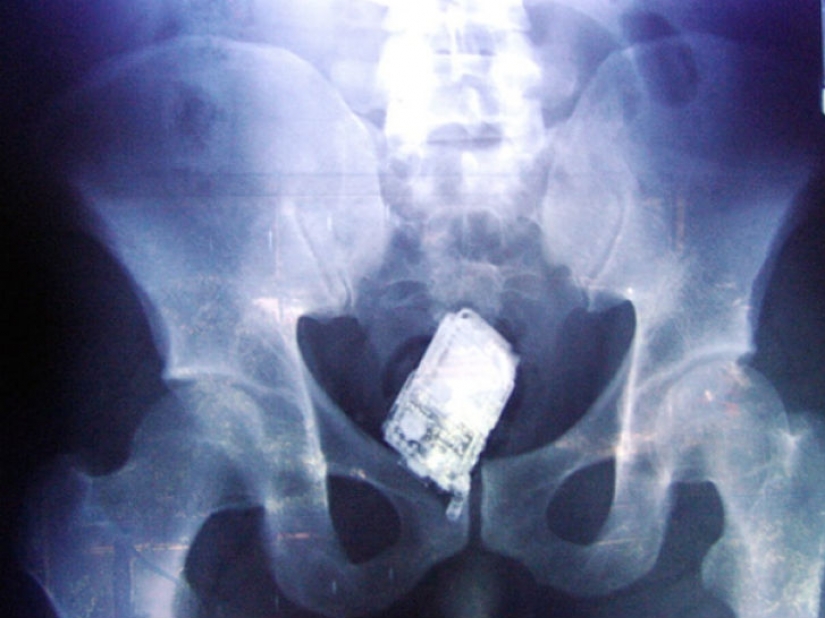

Y los presos de la ingestión de un teléfono celular.